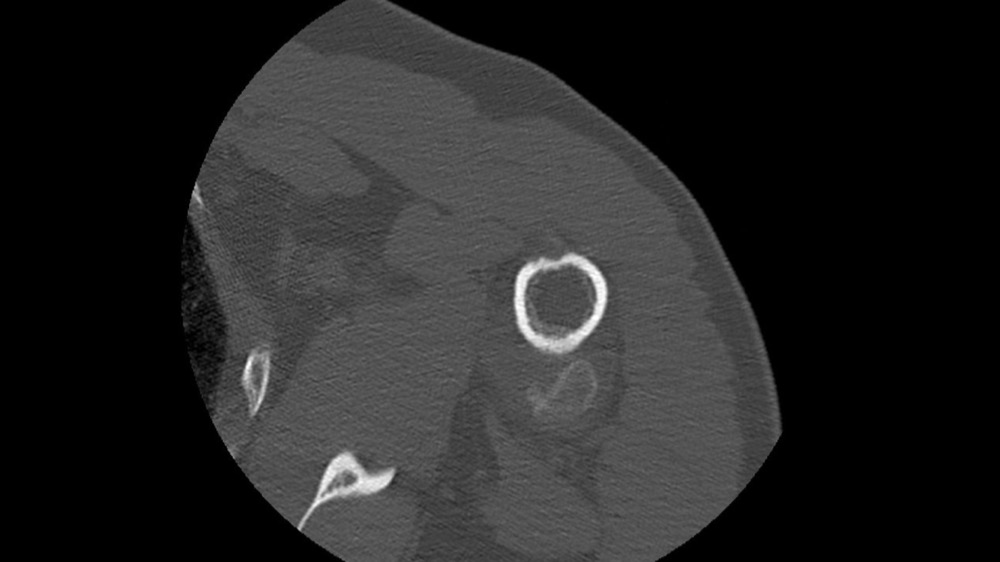

Gortais / Biyoukar / Miquel / Parlier-Cau 19/01/2022